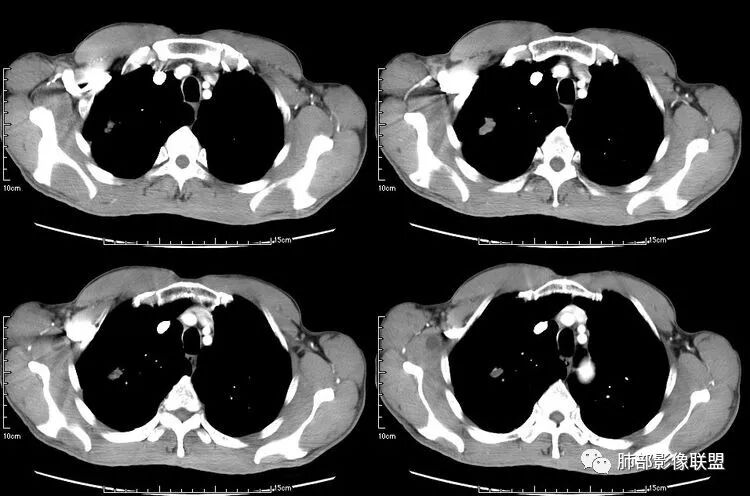

患者老年男性,咳嗽、咳痰、痰中带血伴胸闷2月余。长期大量吸烟史。查肝肾功能、血糖、血脂、心肌酶、电解质、血沉、C反应蛋白、抗“O”、类风湿因子、抗核抗体谱无明显异常。肿瘤标志物提示NSE、CYFRA21-1稍升高。胸部CT:肺气肿背景,左肺下叶后基底段不规则肿块影,见支气管截断,内见大片状低密度区及部分血管影,增强轻度强化,远端空洞形成。双肺多发不规则实性结节影、见毛刺、胸膜牵拉及血管集束,结节内见空洞形成,部分可见血管影,多位于胸膜下。双肺见多发肺大泡。综合考虑左下肺恶性病变并双肺转移。鳞癌或淋巴瘤可能。鉴别血管炎性病变及真菌感染。

左肺下叶团块病灶,有明显张力,增强后病灶内部有可疑延迟强化,看不清楚病灶与支气管的关系,应该支气管受压阻塞了,双肺多发胸膜下小结节,病灶小结节病灶有平行胸膜生长的表现,部分小结节厚壁,部分薄壁,,还有一部分有内容物,这需要两元论,左肺下叶肺癌(腺癌)伴转移,同时合并真菌感染。

无发热,其他慢性细菌先不考虑,有的低毒的,但是结节形态还是比较不规则的,分布也是比较随机,更像原发病灶。真菌方面,结节没有融合,坏死也是液化坏死,不符合隐球菌,曲霉不符合IPA,慢性吸入的也少见。结核没有树丫,不考虑。鉴别主要是GPA,和肺癌。GPA不支持点是皮肤,肾脏没有累及,ANCA不支持。。。肺癌主要是腺癌和鳞癌转移。比较支持的是淋巴结肿大,和左下肺的主病灶,支气管堵塞和异常强化。还有分叶,局部膨隆。可以建议支气管镜检测。

本病例左肺下叶肿块,有深分叶、毛刺、胸膜牵拉凹陷、支气管截断及纵隔内淋巴结肿大等征象,都均支持病灶为恶性,如腺癌,而且叶间裂的多发结节也提示是腺癌来源可能大;双肺多发结节、肿块,大部分病灶有分叶、毛刺及胸膜凹陷的恶性征象,与原发肿瘤本身的性质有关,所以应该与左肺下叶肿块同源,而且双肺多发病灶内空洞也具有多样性;